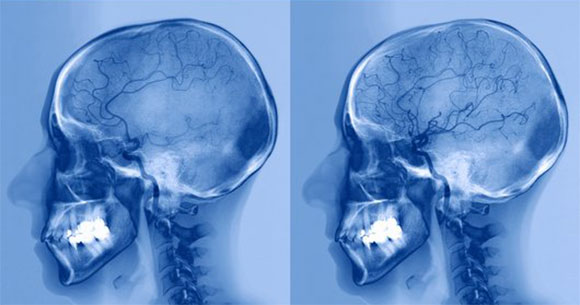

אם אכן קיים חשש ממשי לשבץ מוחי, שולחים בדחיפות את המטופל לסריקות דימות של המוח, שנועדו לזהות חסימות של כלי דם או דימומים, כדי לקבוע אילו אזורים במוח נפגעו ומה היה היקף הפגיעה. הדימות נעשה בשני אמצעים עיקריים. טומוגרפיה ממוחשבת (CT) היא סריקה מהירה למדי המבוססת על חתכים רבים של צילומי רנטגן, ומאפשרת אבחון מהיר של דימום במוח שיאפשר טיפול זריז. סריקת דימות תהודה מגנטית (MRI) היא בדיקה איטית ומדויקת יותר, כך שמשתמשים בה כשהתסמינים מורכבים, כשלא ברור איפה בדיוק אירע השבץ, ולאחר הופעתו של שבץ איסכמי חולף. בשני סוגי הסריקות הרופאים יכולים להזריק למחזור הדם של המטופל חומר שישפר את איכות התמונה ויאפשר תיעוד יסודי של כלי הדם שבמוח.

חולה שבץ עם חסימת עורק (שמאל) ולאחר טיפול (ימין) בתרופות ממיסות קרישי דם. תמונת דימות של מוח לפני ואחרי טיפול בשבץ איסכמי | מקור: ZEPHYR, Science Photo Library